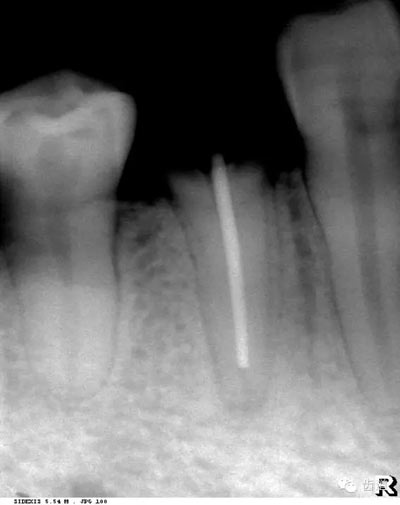

2)營養(yǎng)管:

常見于下頜前牙區(qū),在牙根之間的牙槽骨內(nèi)并與牙長軸平行的密度低的條狀影像。此為小血管進入牙槽突的影像。

3)頦孔:

位于前磨牙根尖區(qū)域,為一大致圓形密度低的影像。頦孔位置變異大,多位于第二前磨牙根尖稍下,注意與根尖周病變區(qū)別,其要點是牙周膜及其骨硬板是否連續(xù)不斷。